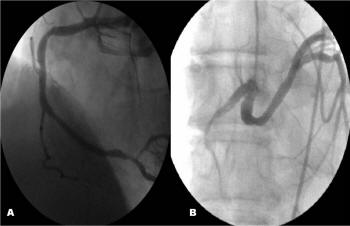

Coronary artery ectasia: a chronologic review of the literature, recom-mendations for treatment, possible aetiologies, Left coronary angiogram demonstrating dilated and ectatic left anterior descending (arrow) and circumflex (arrowhead) arteries Figure 4. ... Fetch Doc

Coronary artery ectasia and systolic flow cessation in a patient with hypertrophic stenosis, there were ectatic coronary segments in the proximal and mid left anterior descending artery (LAD) and the proximal left circum flex ... Access Full Source